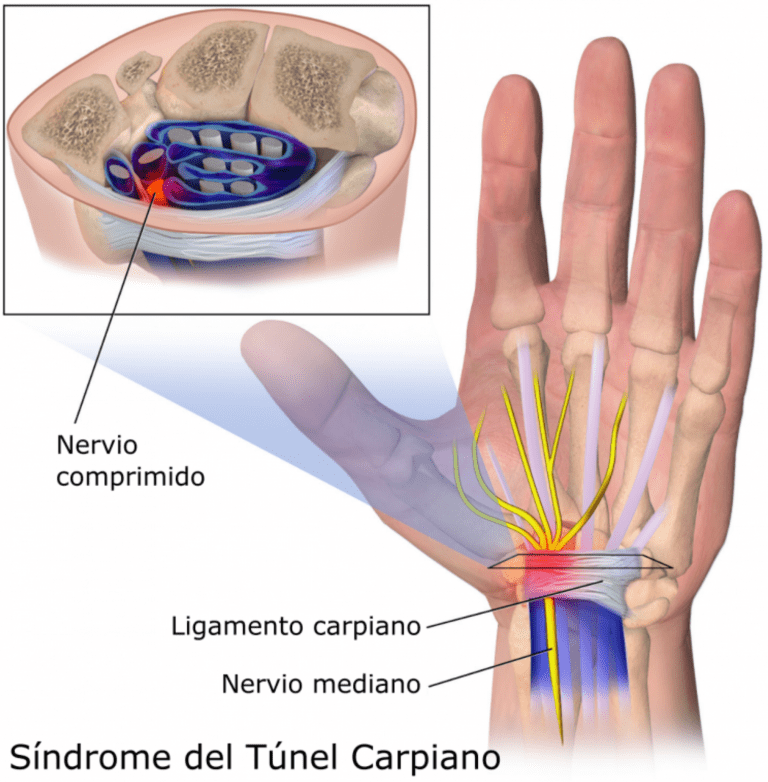

1. Síndrome del Túnel Carpiano

El túnel carpiano es un espacio estrecho situado en la cara palmar del carpo, por el que transcurren varias estructuras por un espacio muy reducido.. Cuando este espacio se reduce más aún debido a la inflamación, puede producirse lo que conocemos como Síndrome del Túnel Carpiano.

Este síndrome se produce por una neuropatía de atrapamiento del nervio mediano a su paso por el túnel carpiano. Su causa es desconocida, aunque se suele asociar a movimientos y esfuerzos de repetición.